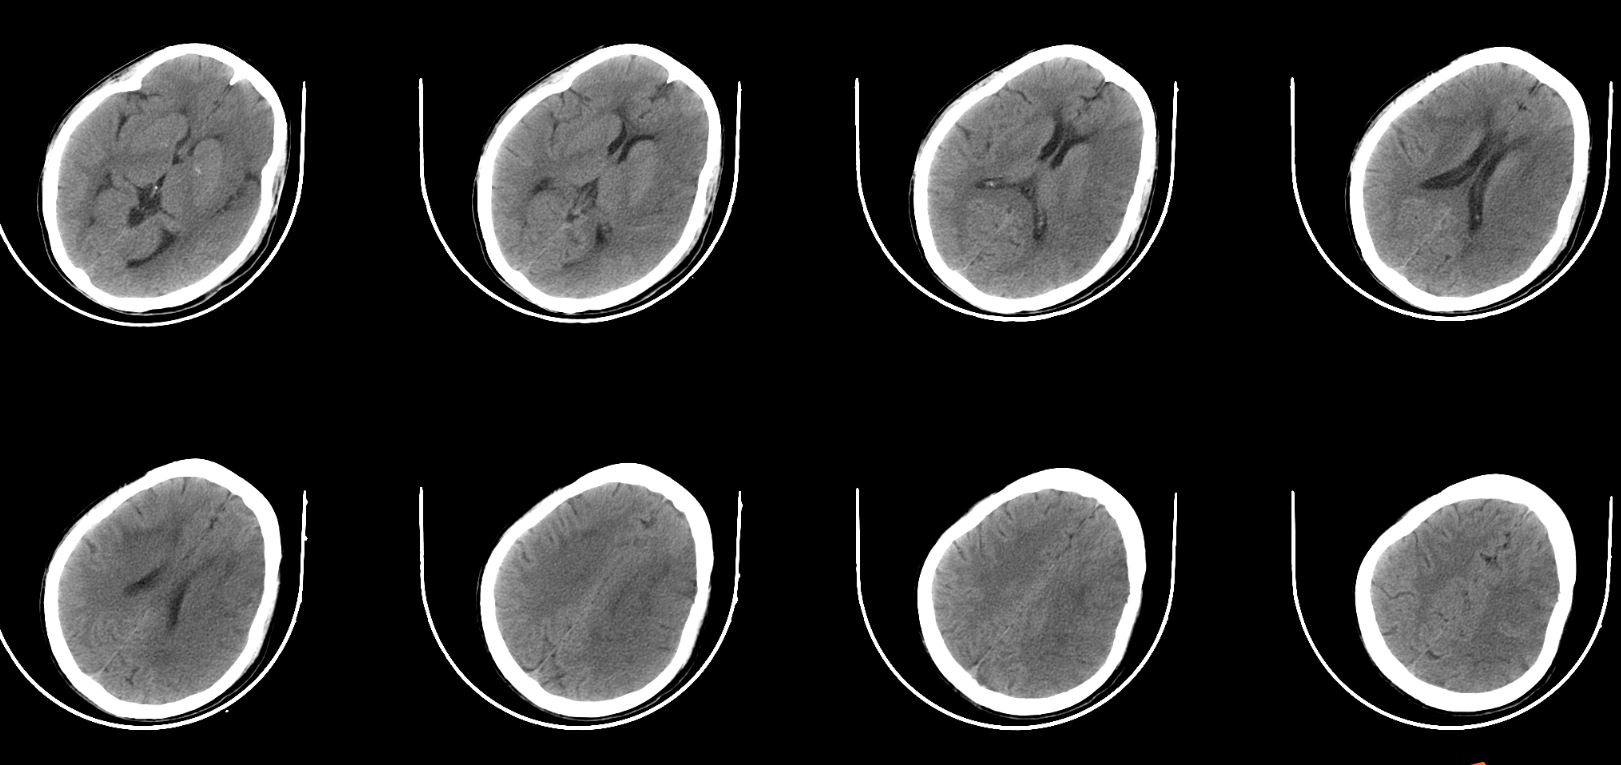

查体:神志昏睡、精神差、急性重症病容。GCS评分E2V3M5=10分,吐词不清,右侧口角、鼻唇沟变浅,示齿、伸舌不合作,双耳听力不合作,疼痛刺激能模糊定位,右侧肌力2级,左侧肌力5级,左侧病理征阴性。NIHSS评分:18分。ASPECT大脑中动脉评分2分。

进一步完善头颈部CTA检查,提示左侧颈内动脉闭塞。

虽CTA提示颅内段颈内动脉及左侧颈内动脉颅内分支无明显缺失,但大脑中动脉远端分支明显稀疏,显影不佳。再结合头颅磁共振了解代谢情况。

复查CT无出血,无造影剂外渗,病灶范围较大,侧脑室受压,适当脱水,控制颅内压,考虑大面积梗死,又是ICAS,选择使用单抗。

此次复查患者颅内水中完全消退,片中所示低密度灶范围较术前明显减少,结合患者症状表现,患者明显获益。